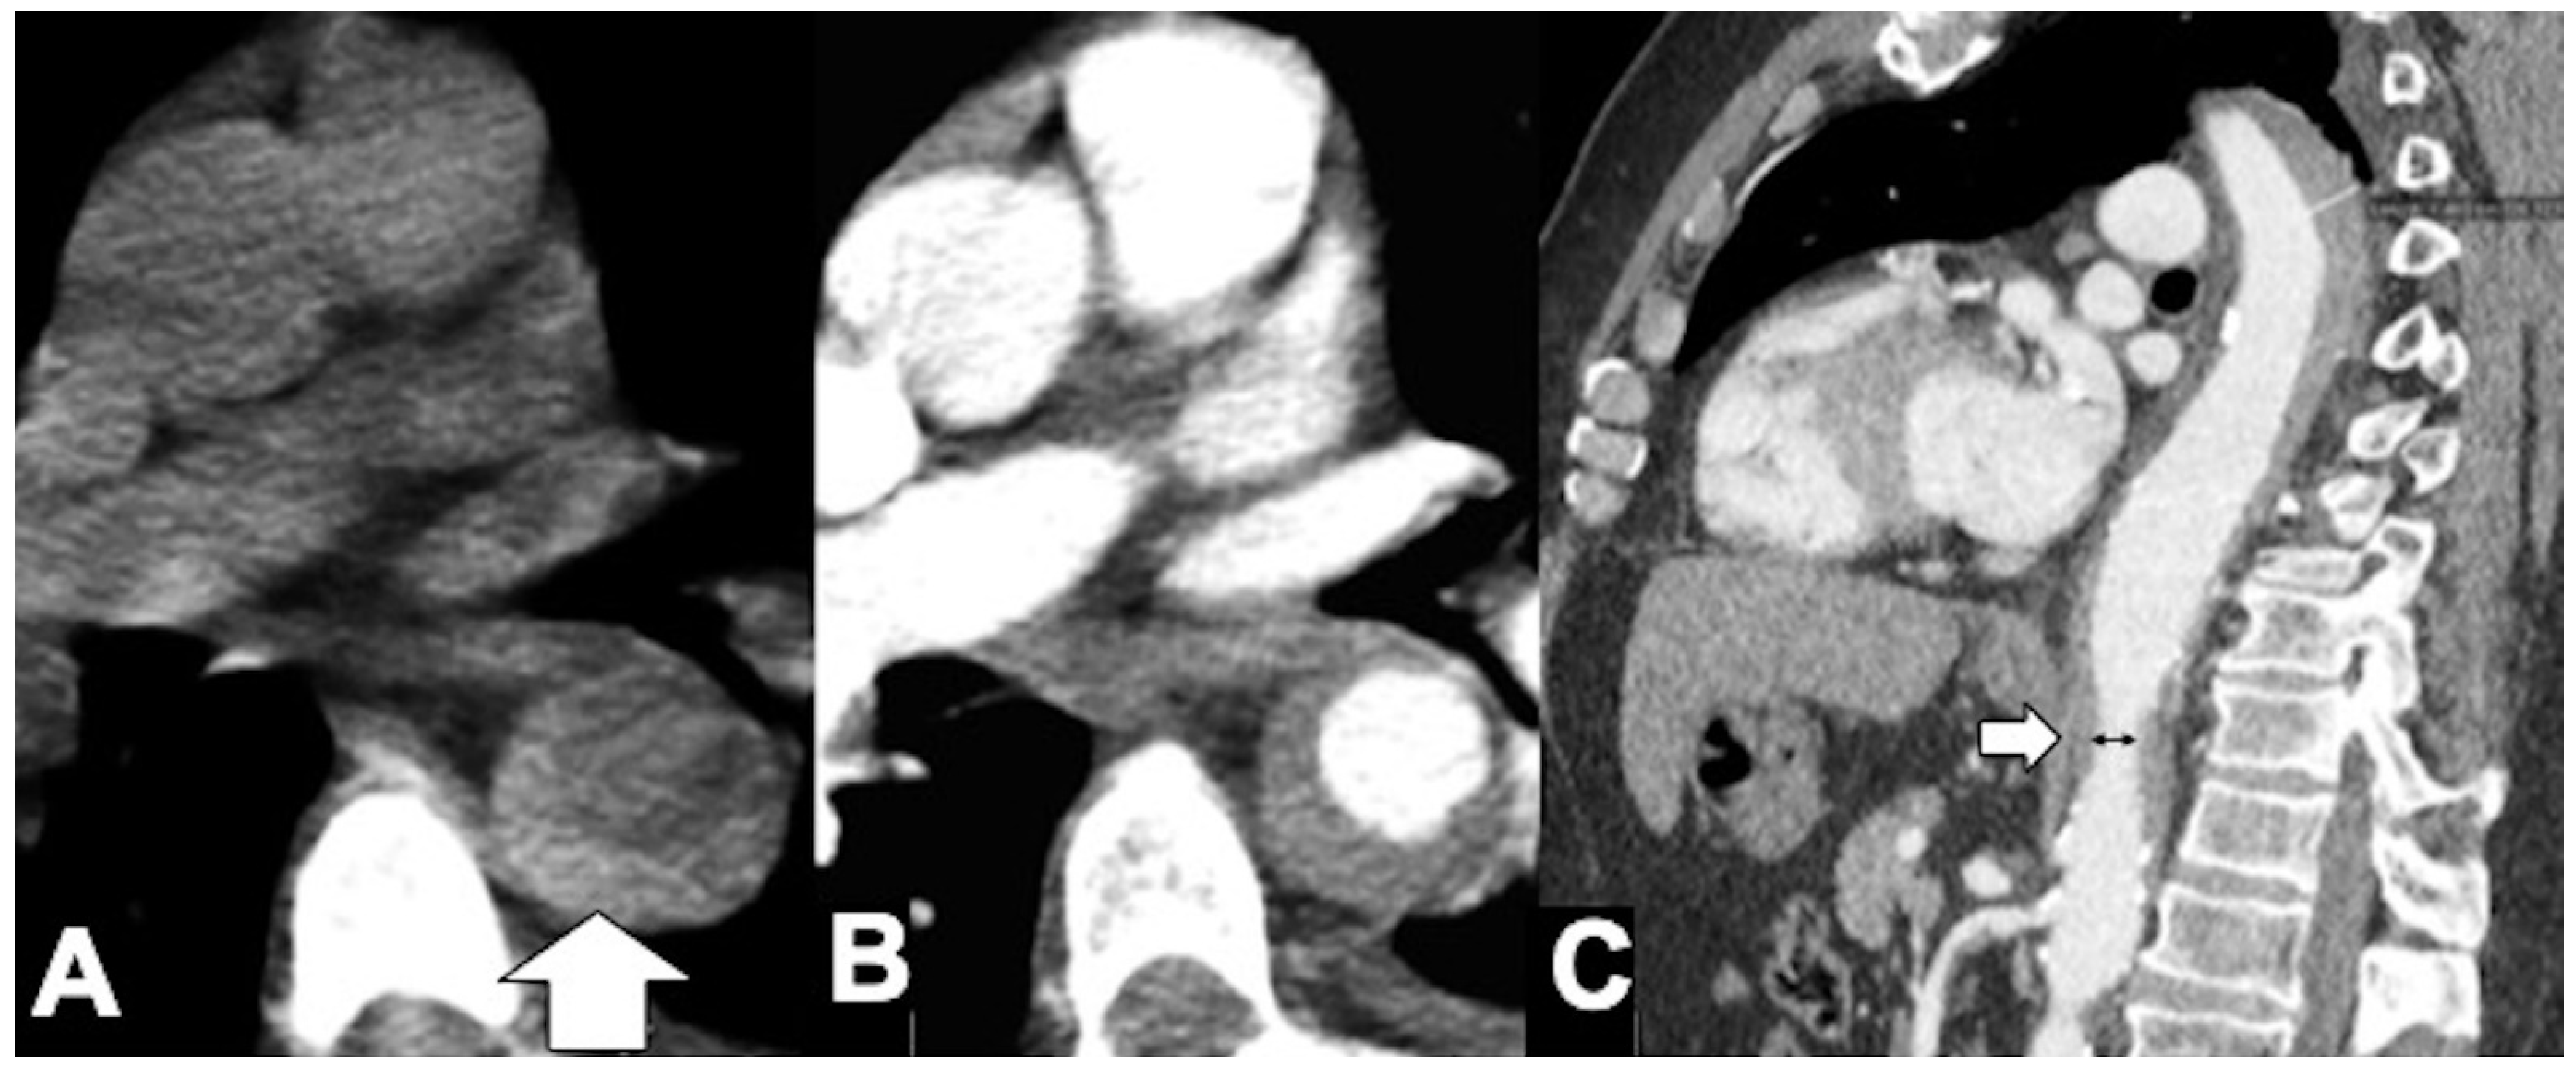

Figure 8. CT features of acute type B IMH in a 62-year-old man with abrupt chest pain and Type B IMH at baseline CTA examination. (A) Axial low-dose unenhanced CT image shows hyperdense crescent sign of the aortic wall (arrow). (B) Axial arterial phase CTA image in the same patient shows decreased diameter of the aortic lumen and the smooth luminal-wall interface. (C) Sagittal reconstruction CTA image shows decreased diameter of the aortic lumen (arrow) and a relative constant circumferential relationship with the wall.